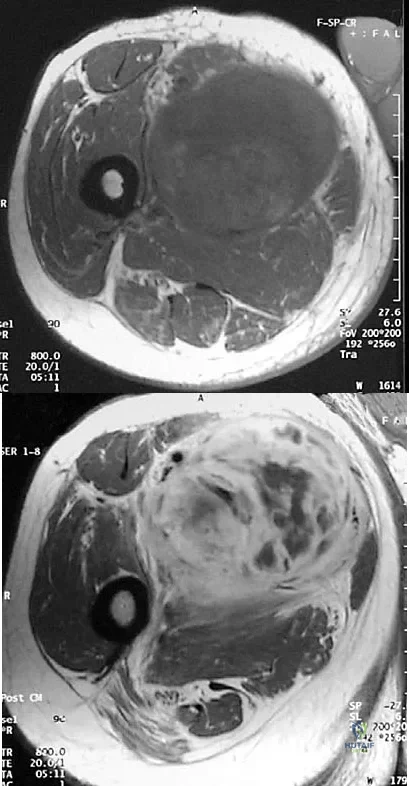

An athletic 55-year-old man reports a painless mass in the anterior aspect of the thigh that appeared 3 weeks ago and has not changed in size. The patient denies any history of trauma. Examination reveals a firm, well-defined nontender mass in the anterior thigh and no inguinal adenopathy or cutaneous changes. Plain radiographs are unremarkable. T1- and T2-weighted MRI scans are shown in Figures 44a and 44b. What is the most likely diagnosis?

Explanation